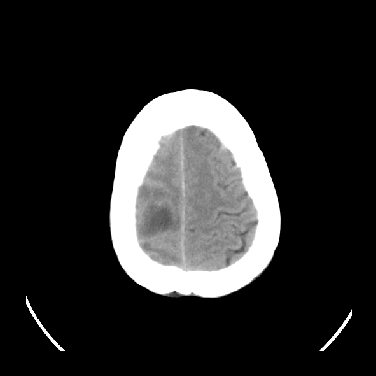

男,45岁,左侧肢体乏力1周。ex:胸片示:两肺团块状、斑片状密度增高影,其内可见小空洞。支纤镜、经皮肺穿示:干酪样物。

结合病史考虑结核性脑炎脑膜炎,伴脑脓肿形成

考虑右侧顶叶脑脓肿形成。

同意“考虑结核性脑炎脑膜炎,伴脑脓肿形成”的意见,不轻易怀疑肿瘤。

考虑结核性脑炎脑膜炎,伴脑脓肿形成。

考虑右侧顶叶脑脓肿(结核性?)。

结核性脑脓肿可能大

结合病史考虑结核性脑炎脑膜炎,伴脑脓肿形成,囊变转移瘤不除外